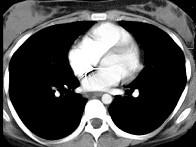

7岁,男,发热、消瘦,数月前触及颈部淋巴结肿大,CT和MR检查如图,请选择最可能的诊断 ( )A.淋巴瘤B.结节病C.淋巴结核...

问题 7岁,男,发热、消瘦,数月前触及颈部淋巴结肿大,CT和MR检查如图,请选择最可能的诊断 ( )

选项 A.淋巴瘤 B.结节病 C.淋巴结核 D.转移性淋巴肿大 E.胸腺瘤

答案 A